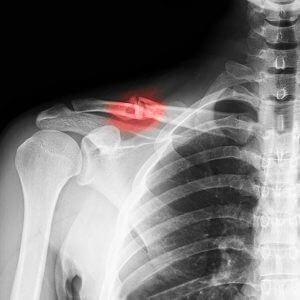

Диагностика

Установить тип перелома можно с помощью диагностики. В этом случае потребуется рентгенография верхней части грудной клетки. Врач, оценив степень смещения и локализацию перелома, выберет наиболее подходящий метод лечения.